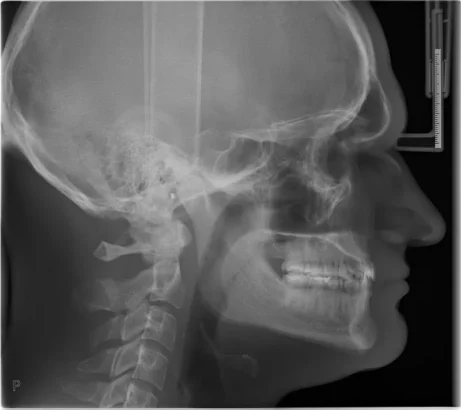

Ortodoncie

OP 3D EX s kefalometrickým modulem nabízí potřebné protokoly, jako jsou laterální a pediatrické laterální projekce (s nastavitelnou šířkou zorného pole od 16 do 26 cm), zadopřední (PA) projekce a snímkování karpu* – to vše s rychlými časy skenování a při nízké dávce záření.

* Snímkování karpu je volitelný zobrazovací program.